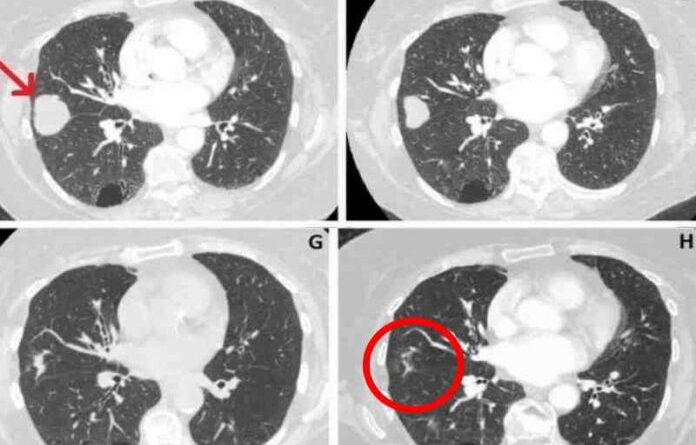

Após receber tratamento com canabidiol (CBD), o tumor no pulmão direito de uma idosa de 80 anos do Reino Unido reduziu 76%.

O câncer foi descoberto em junho de 2018, com 41 mm. Em março deste ano o tamanho era de 10mm.